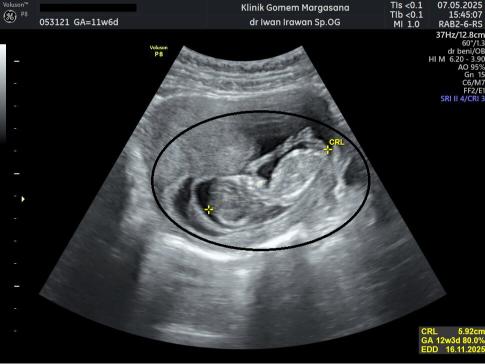

USG Janin 11 Minggu

USG di trimester ke-3 sangat penting untuk memantau posisi bayi, volume air ketuban, and fungsi plasenta. Pastikan janin dalam posisi kepala di bawah dan tidak ada lilitan tali pusat yang mengganggu pergerakannya.